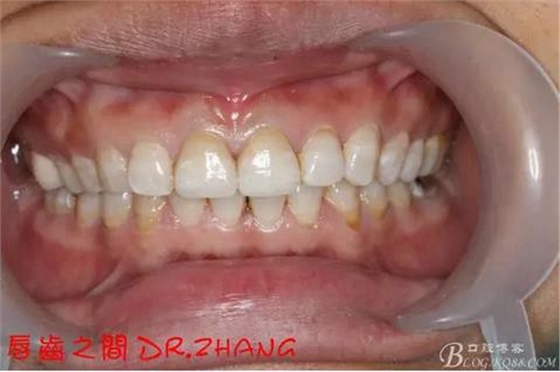

復(fù)診:臨時(shí)牙良好 患者自訴無(wú)不適癥狀 去除臨時(shí)修復(fù)體 排齦 清理牙面 試戴全瓷修復(fù)體后粘結(jié) 常規(guī)醫(yī)囑 不適隨診

總結(jié):沒(méi)有術(shù)前照片 預(yù)備牙體過(guò)長(zhǎng) 顏色還是有差距